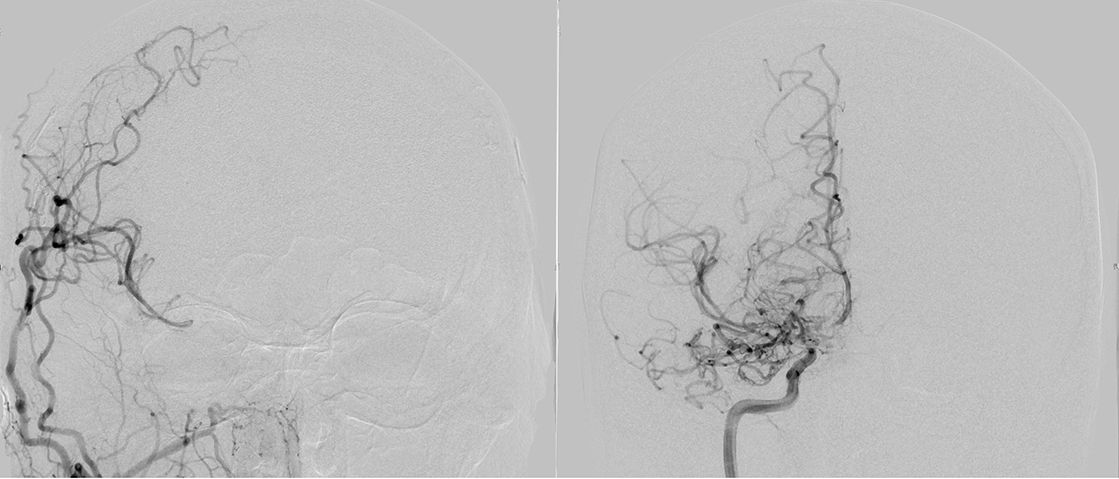

Alle VideosDer Name „Moyamoya“ stammt aus dem Japanischen und bedeutet übersetzt „Rauchwolke“, was auf das diffuse Erscheinungsbild feiner Kollateralgefäße in der Gefäßdarstellung „Angiographie“ zurückzuführen ist.

Mehr erfahrenMoyamoya wurde 1957 erstmals von den Japanern Takeuchi und Shimizu beschrieben. Die Erkrankung kommt vor allem im asiatischen Raum (insbesondere Japan und Korea) häufiger vor, wobei man von einem Auftreten (Inzidenz) von ca. 0.35/100.000 Einwohnern/Jahr ausgegangen wird. Für den europäischen Raum gibt es bis heute keine verlässlichen Daten, jedoch schätzt man, dass die Erkrankung hier ca. 10x seltener als oben genannt vorkommt. Der Name „Moyamoya“ stammt aus dem Japanischen und bedeutet übersetzt „Rauchwolke“, was auf das diffuse Erscheinungsbild feiner Kollateralgefäße in der Gefäßdarstellung „Angiographie“ zurückzuführen ist.

Die konventionelle cerebrale Angiographie ist die wichtigste Untersuchung zur Diagnosestellung der Moyamoya Krankheit. Diese Untersuchung ist zu vergleichen mit einer Herzkatheteruntersuchung, eben nur mit Darstellung der Hirnarterien. Bei Moyamoya-Patientinnen und Patienten werden, im Gegensatz zu Routineuntersuchungen bei anderen cerebralen Erkrankungen, selektiv die vordere und hintere Zirkulation des Gehirns dargestellt, sowie auch die Versorgung der extrakranialen Gefäße. Diese umfassende Darstellung ist besonders wichtig, um die vollständige Ausdehnung der Erkrankung zu erfassen und alle möglicherweise veränderten Blutflüsse im Gehirn zu verstehen. Je nach Befund werden die Engstellen der Hirnarterien, sowie auch mögliche begleitende Veränderungen selektiv hochauflösend dreidimensional dargestellt. Es ist wichtig zu erwähnen, dass die Moyamoya Krankheit nicht über eine Katheterintervention (Ballonaufweitung der Engstelle) behandelt werden kann und darf. Dies haben mehrere Studien gezeigt.

Ist eine operative Behandlung notwendig, wird zumeist ein direkter extrakranieller-intrakranieller Bypass (Verbindung eines außerhalb des Schädels liegenden oberflächlichen Gefäßes, mit einem oberflächlichen Hirngefäß; sogenannter EC-IC Bypass) angelegt. Da der Durchmesser des Spendergefäßes und auch des Gefäßes an der Hirnoberfläche meist ca. 1mm beträgt, bedarf es hier viel Erfahrung um die hauchdünne Gefäßwand nicht zu beschädigen. Mit hierfür speziell angefertigten äußerst feinen Instrumenten werden die beiden Gefäße unter dem hochauflösenden Operationsmikroskop mit mehreren 0.02mm dünnen Fäden End-zu-Seit verbunden. Zum Vergleich: Ein menschliches Haar hat einen Durchmesser von 0.06-0.1 mm. Sobald die Verbindung hergestellt ist, wird das Gehirn mit zusätzlichem Blut versorgt und somit weiteren Schlaganfällen vorgebeugt.